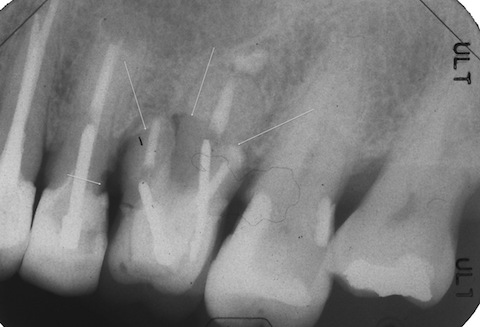

http://plaza.rakuten.co.jp/mabo400dc/diary/201508110000/この時の続きを見たいというリクエストがありましたので、CKを作る過程を2回シリーズで特集します。抜歯再植というのは、これ以外に保存の手だてが無いと思われるケースが適応症なのですが、多いです^^;歯根破折の他に、例えばうちでも、他院でもエンド治療が上手くいかない場合にはこれしかないのです。僕が「ちくわ」とよんでいる症例などです。http://plaza.rakuten.co.jp/mabo400dc/diary/201201090002/70代女性、右下6遠心根の抜歯再植から2ヶ月経過。印象してセットしました。動揺度1なので、これで終わりではなく、右隣の5番のCKを再制作するついでに、被せ連結する予定です。つづく